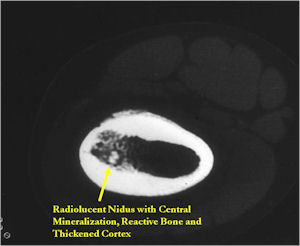

CT Scan:

- Well defined nidus with a smooth peripheral margin; +/- mineralization (CT more sensitive than XR and MRI for detecting mineralization); CT is better for detecting nidus in presence of exuberant sclerosis

- Radiographic Presentation